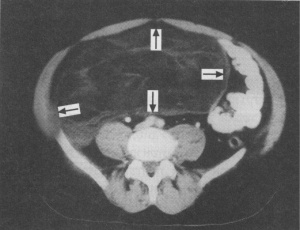

בטומוגרפיה ממוחשבת של הבטן ניתן לראות שאת ענקית, המאופיינת לעתים בנמק מרכזי הדוחק את איברי הבטן (תצלום 4.2).

שאת בעלת פוטנציאל ממאיר, השכיחה בעיקר ברטרופריטונאום, בייחוד בגילאי 40 - 80 שנה, וגדלה לממדים גדולים מאוד. לשאת זו אין קופסית מגבילה. בטומוגרפיה ממוחשבת אפשר לראות את ממדי השאת הדוחקת את איברי הבטן (תצלום 5.2).